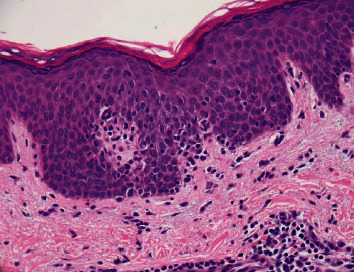

X-linked agammaglobulinemia (XLA) is a genetic disorder with mutation in Bruton's tyrosine kinase (BTK). Defects in B cell development and immunoglobulin production lead to recurrent infections following loss of maternal IgG at 6 months of age. A 55-year-old male with a longstanding common variable immunodeficiency diagnosis on infusion therapy presented to the clinic with cutaneous T-cell lymphoma, which inspired overall repeat evaluation. Immunoglobulin levels and lymphocyte markers, family history, and genetic testing prompted a true diagnosis of XLA and novel mutation in the BTK gene. Disease-associated mutations have been noted in all five domains of BTK, with missense variants most commonly cited among the 100s of reported genetic alterations. The BTK protein is expressed in hematopoietic lineages and plasma cells, with the exception of T lymphocytes. Disruption in the protein function or absence of BTK halts normal B cell development at the pre-B transitional cell stage and induces premature apoptosis. We present the first reported case of a novel hemizygous BTK c.1492C > G mutation in a patient causing XLA.

Abstract Image